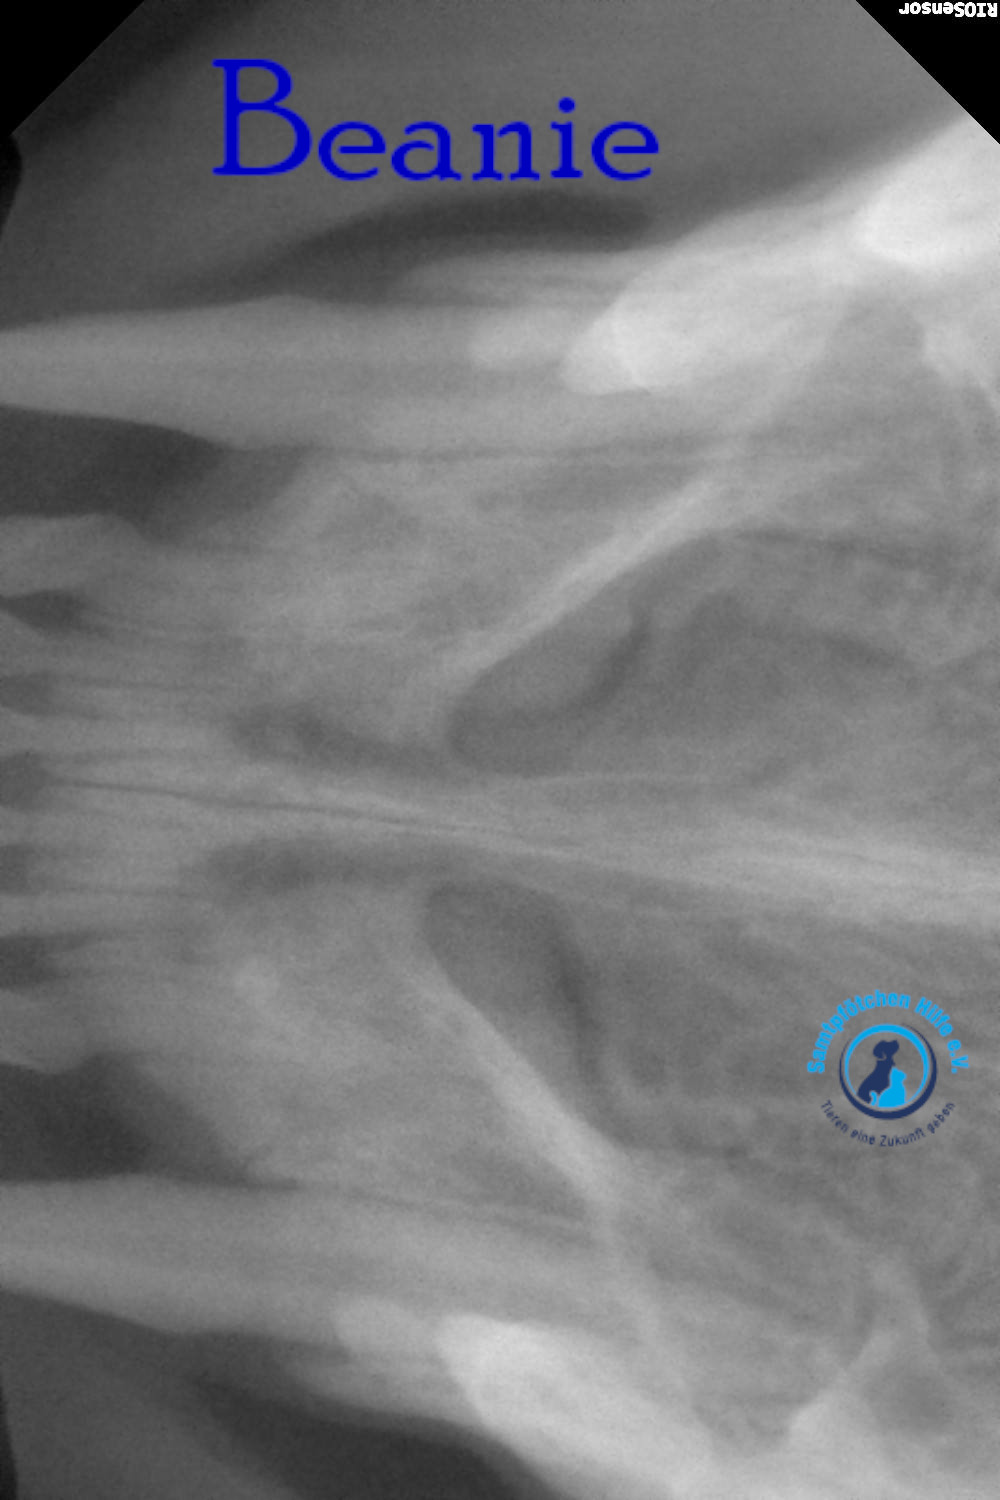

Unsere Beanie hat immer noch Probleme mit der Nasenatmung und musste deshalb zum Tierarzt. Der Arzt nahm Blut für allgemeine Indikatoren und Biochemie sowie PCR für Leukämie und Immunschwäche ab. Auch die Ohren wurden sorgfältig untersucht; Manchmal behindern Polypen in den Ohren die Atmung, aber die Ohren waren sauber. Der Arzt untersuchte auch den Rachenraum. Aufgrund der Untersuchungsergebnisse wurde eine Computertomographie des Gehirns im Bereich der Nase und des Nasenrachens sowie eine tägliche Zahnreinigung verordnet – bei Beanie besteht der Verdacht auf eine juvenile Stomatitis. Wenn Sie jetzt nicht mit der Zahnbehandlung beginnen, müssen in 2-3 Jahren alle Zähne gezogen werden.

Lyudmila schreibt: "Die Ärzte vermuteten, dass etwas in Beanies Nasenrachenraum feststeckte, ein Fremdkörper, der sie am Atmen hinderte. Sie führten eine Operation durch, führten eine Sonde tief ein und spülten sie aus, konnten aber nichts finden. Eine Röntgenaufnahme zeigte leichte Veränderungen in einer Nasennebenhöhle. Außerdem wurde Material aus der Nasenschleimhaut für eine Zytologie entnommen. Das Fazit des Zytologen: Das Material könnte auf einen Polypen in der Nase hinweisen. Da Binis Nasengänge sehr eng sind, ist eine Rhinoskopie möglicherweise nicht möglich. Bisher wurden Hormontropfen in die Nase empfohlen, die aber kaum helfen. Eine Konsultation mit einem Chirurgen, der Rhinoskopie durchführt, ist erforderlich; unsere Tierklinik führt diese Untersuchung nicht durch.